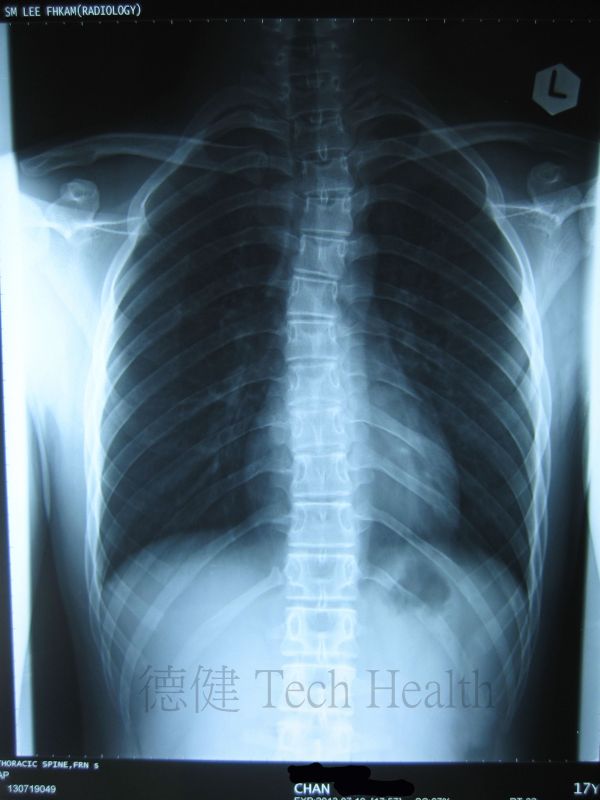

個案二 - 陳先生 18歲 - 胸椎側彎。

- 2013-7-29 患者時有困倦無力,肩背酸痛,頸胸椎活動受限,咳嗽或深呼吸時不適,胸悶胸痛,腹脹,下肢循環不佳,X片示胸椎側彎。集中治療頸胸椎及頭肩。